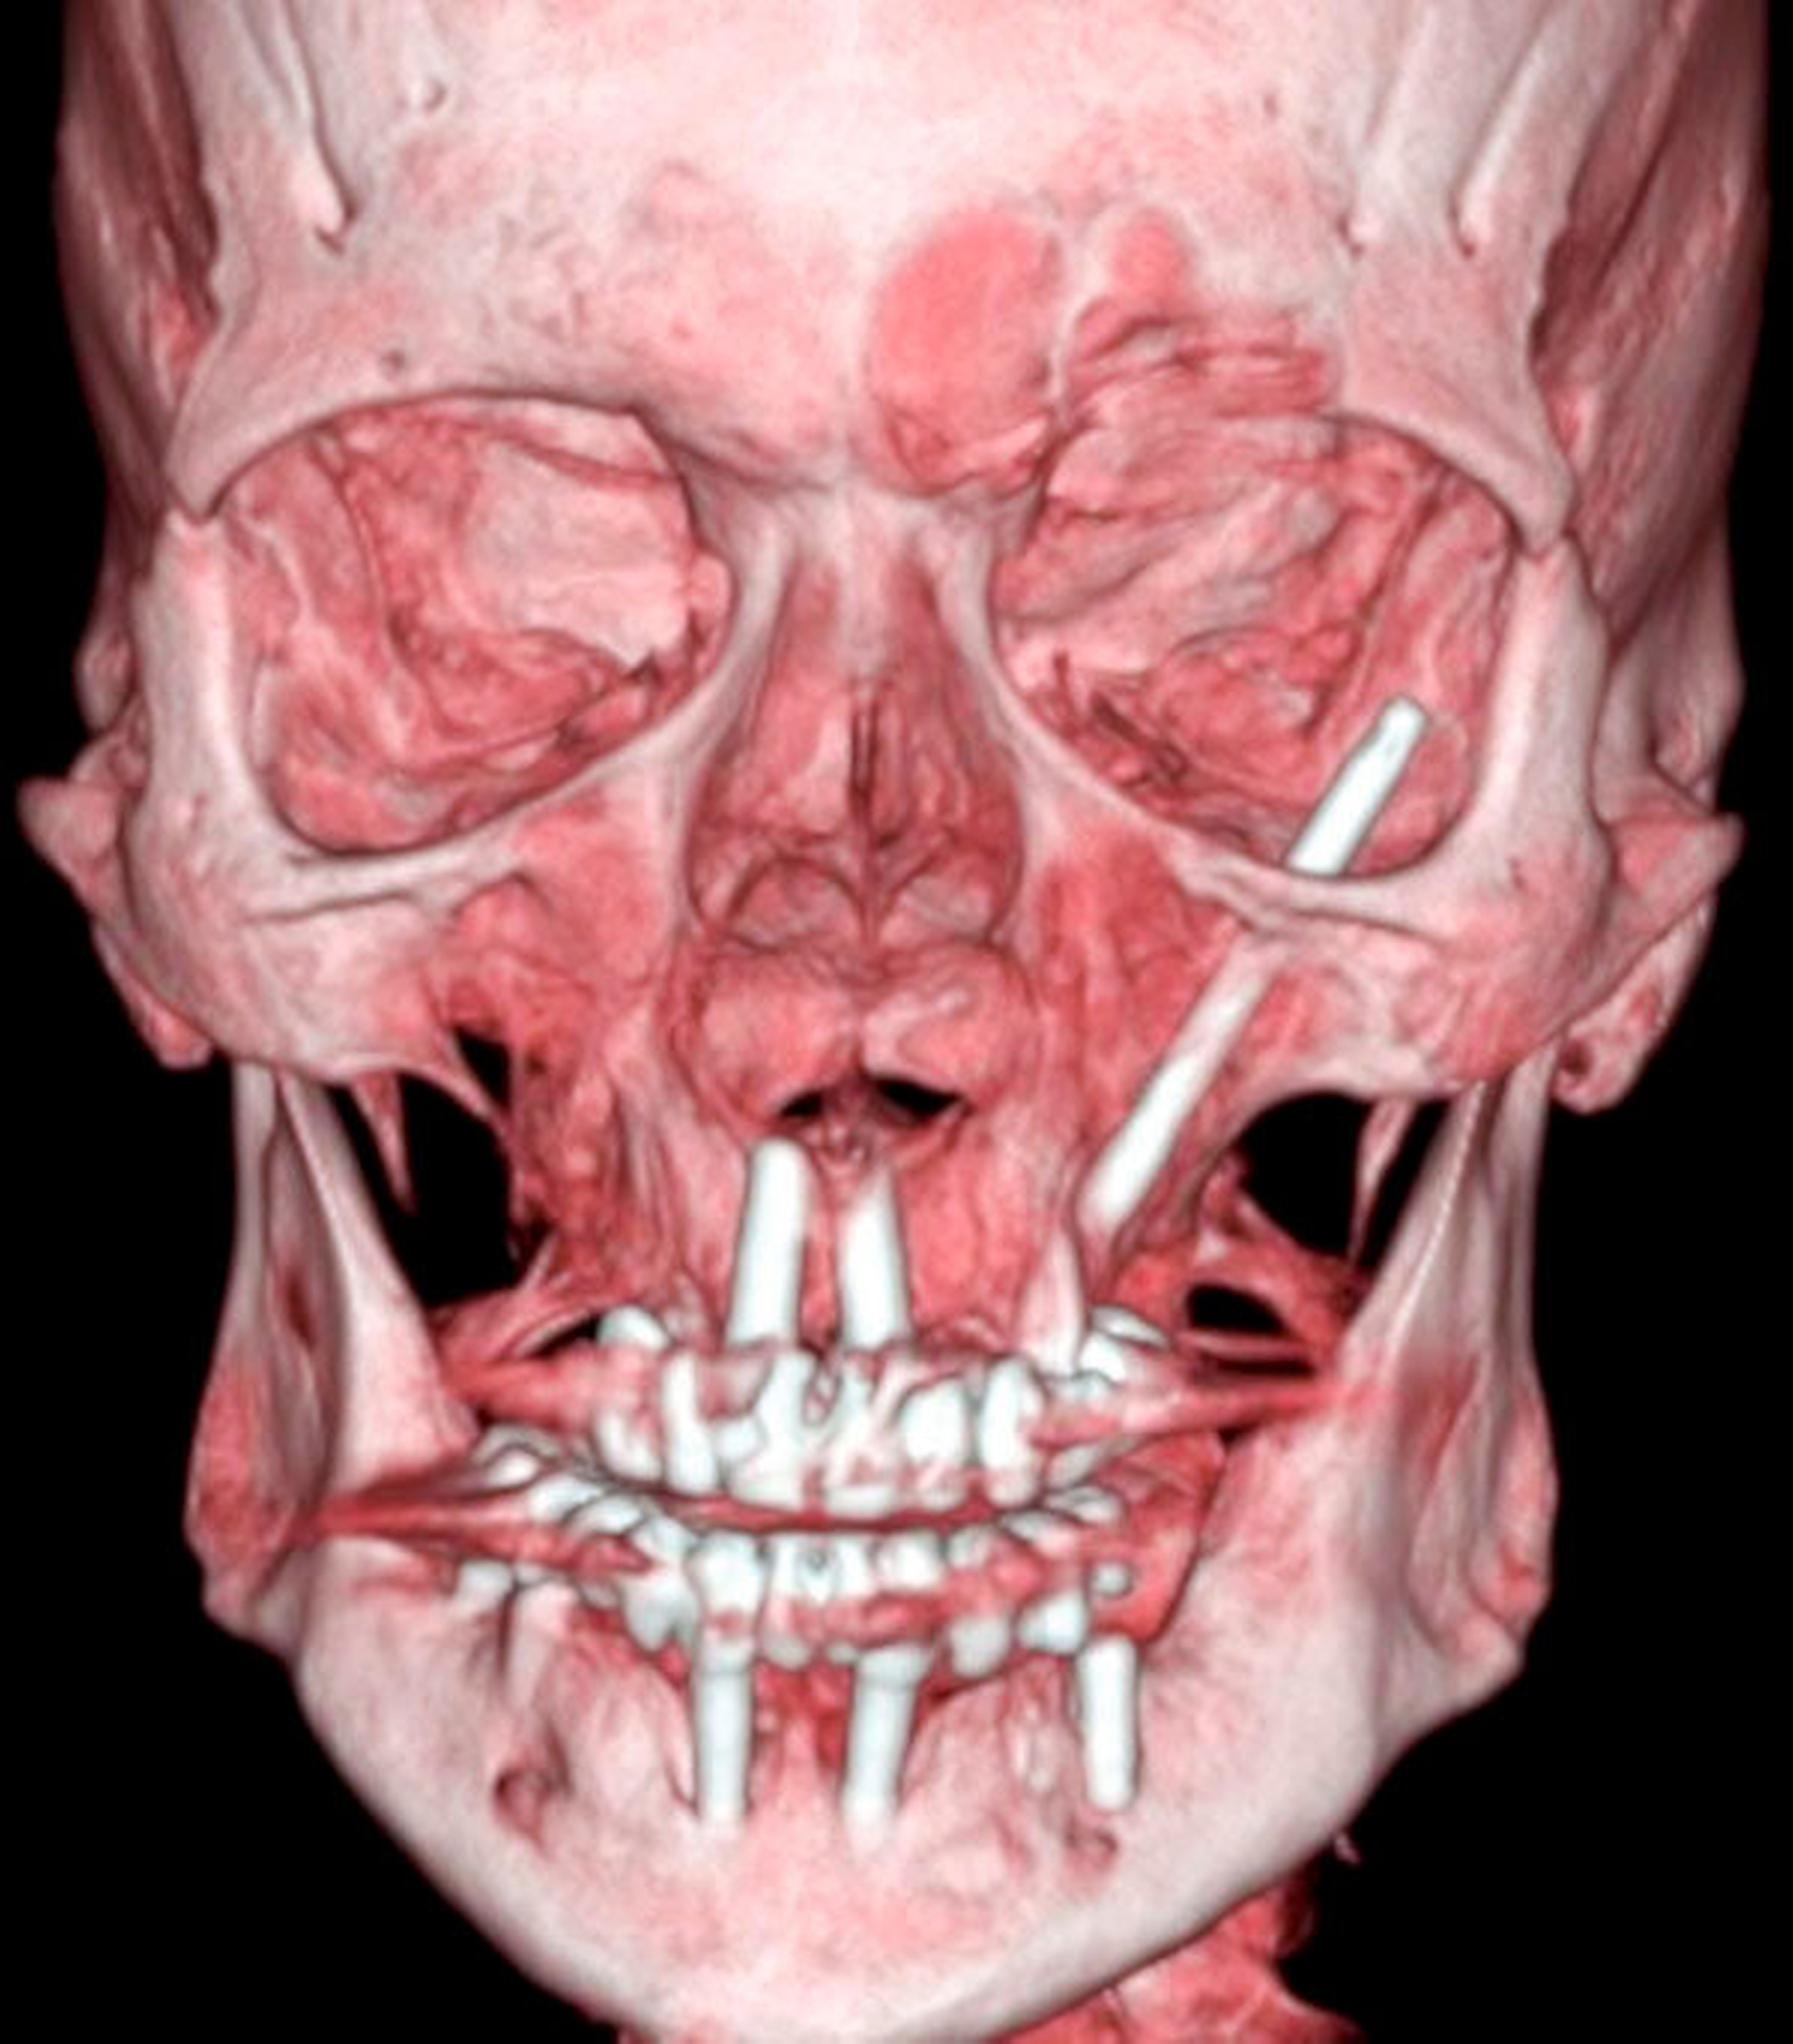

Wegen der unklaren Genese der akuten entzündlichen Veränderungen in der Orbital- und in der Periorbitalregion wurde eine CT- Diagnostik des Schädels mit Kontrastmittelgabe zum Ausschluss einer akuten retrobulbären Raumforderung veranlasst. Hierbei fand sich ein hochgradiger Verdacht auf eine Abszedierung in der rechten Orbita mit dem klinischen Bild von Protrusio bulbi und entzündlicher Mitreaktion der Augenmuskeln M. rectus lateralis und M. rectus inferior. Diese Veränderungen waren auch der Grund für die Weichteilschwellung am Unterlid. Ein intraorbitales Hämatom ließ sich ausschließen.

Zur weiteren Abklärung erfolgte nach zweidimensionaler Beurteilung die dreidimensionale Rekonstruktion der CT-Daten. Hierbei kamen die röntgenopaken Implantate im Kiefer sehr gut zur Darstellung und konnten in Bezug auf deren anatomische Lage beurteilt werden. Im atrophen Ober- und Unterkiefer zeigte sich ein mittelgradiger horizontaler Knochenabbau mit vertikalen Einbrüchen an allen Implantaten. In der rechten Maxilla regio 016 bestand nach Explantation eines rechtsseitigen Zygoma-Implantats ein circa 2 cm großer Defekt, der, aufgrund der verdrängten Weichgewebe und Lufteinschlüsse sicher bis in die mittlere, zentrale Orbita reichte.

Als auffälliger Nebenbefund fand sich auch auf der linken Seite ein 60-mm-Zygoma-Implantat, das 17 mm in die linke Augenhöhle ragte. Neu aufgetretene Veränderungen oder Behinderungen in diesem Bereich waren vom Patienten subjektiv nicht wahrgenommen worden, die Implantation selbst lag bereits zehn Jahre zurück.